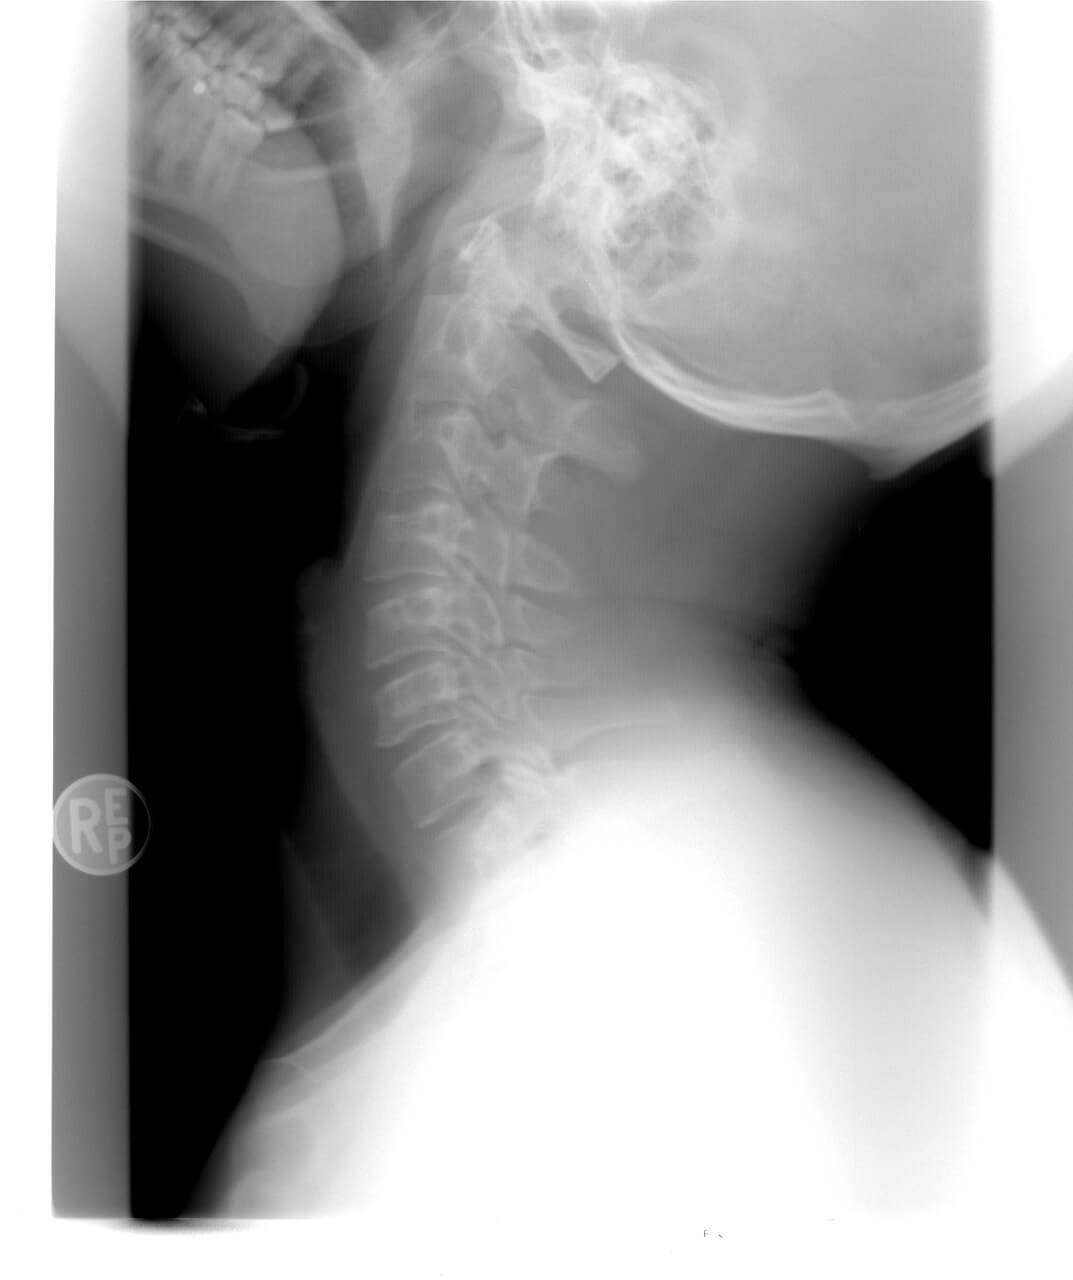

2. 경추 추간판 탈출증: 경추 추간판이 빠져나와 신경을 압박하여 통증유발

3. 경추 척추증: 경추 디스크 퇴행, 뼈 돌기 생성 등으로 인한 통증